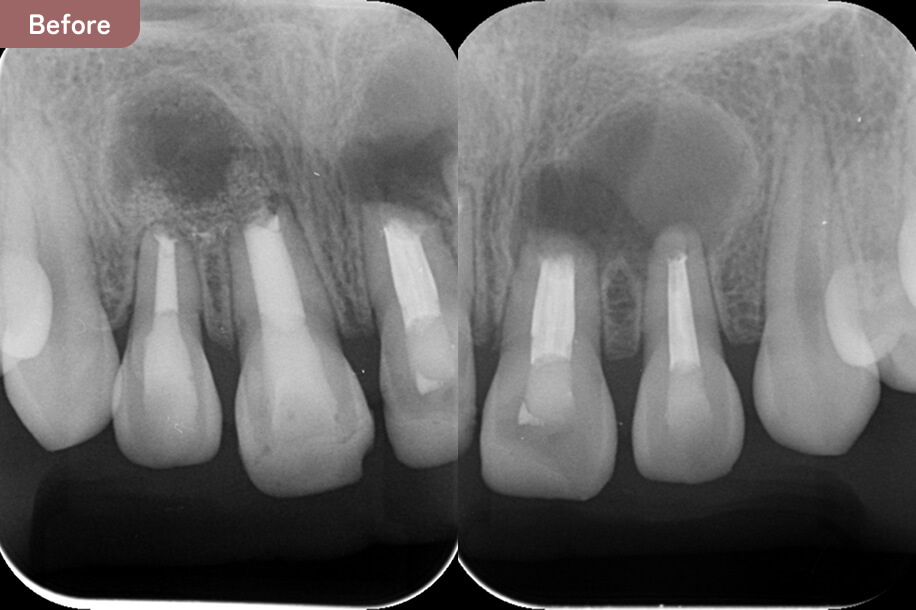

大学病院でも治らず、根の先に大きな骨吸収があり腫れていた。

自費根管治療と歯根端切除術を行い、骨の再生が起こり、症状がなくなった。